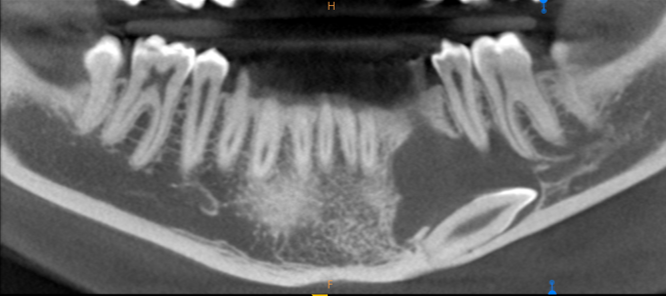

Tras estos hallazgos se solicitóun estudio mediante CBCT mandibular completo, que reveló los siguientes hallazgos en los cortes panorámicos: lesión radiotransparente delimitada y con un halo esclerótico casi completo, que se extiende en sentido mesiodistal desde la zona distal del canino temporal hasta el ápice del primer molar alcanzando la basal mandibular incluyendo la presencia de un canino mandibular (Figura 2).

Los cortes ortorradiales ofrecieron información sobre la ausencia de expansión de corticales, conservación de la cortical lingual y a la altura del segundo premolar ligera perforación de la cortical vestibular (Figuras 3A y 3B). Las reconstrucciones 3D corroboraron los hallazgos anteriormente descritos (Figuras 4A y 4B).